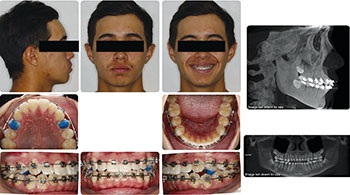

The second case is a 17-year-old male. Despite the crowding and protrusion, I felt that non-extraction treatment had a reasonably good chance of success. I initially flipped his upper incisor brackets in anticipation of needing negative torque. However, the progress records from the pan/repo/ceph appointment at seven months revealed to me that continuing with the non-extraction plan in my hands was not prudent. I did not feel confident that, even with the prospect of safely pushing the limits of IPR and negative torque, I would be able to position his upper incisors in an ideal AP and labiolingual position. The decision was made at that appointment to un-flip (reposition) the upper incisor brackets and refer for the extraction of his upper first bicuspids and lower second bicuspids. The treatment was completed in 25 months, resulting in a favorable position of his upper incisors within his face and smile.